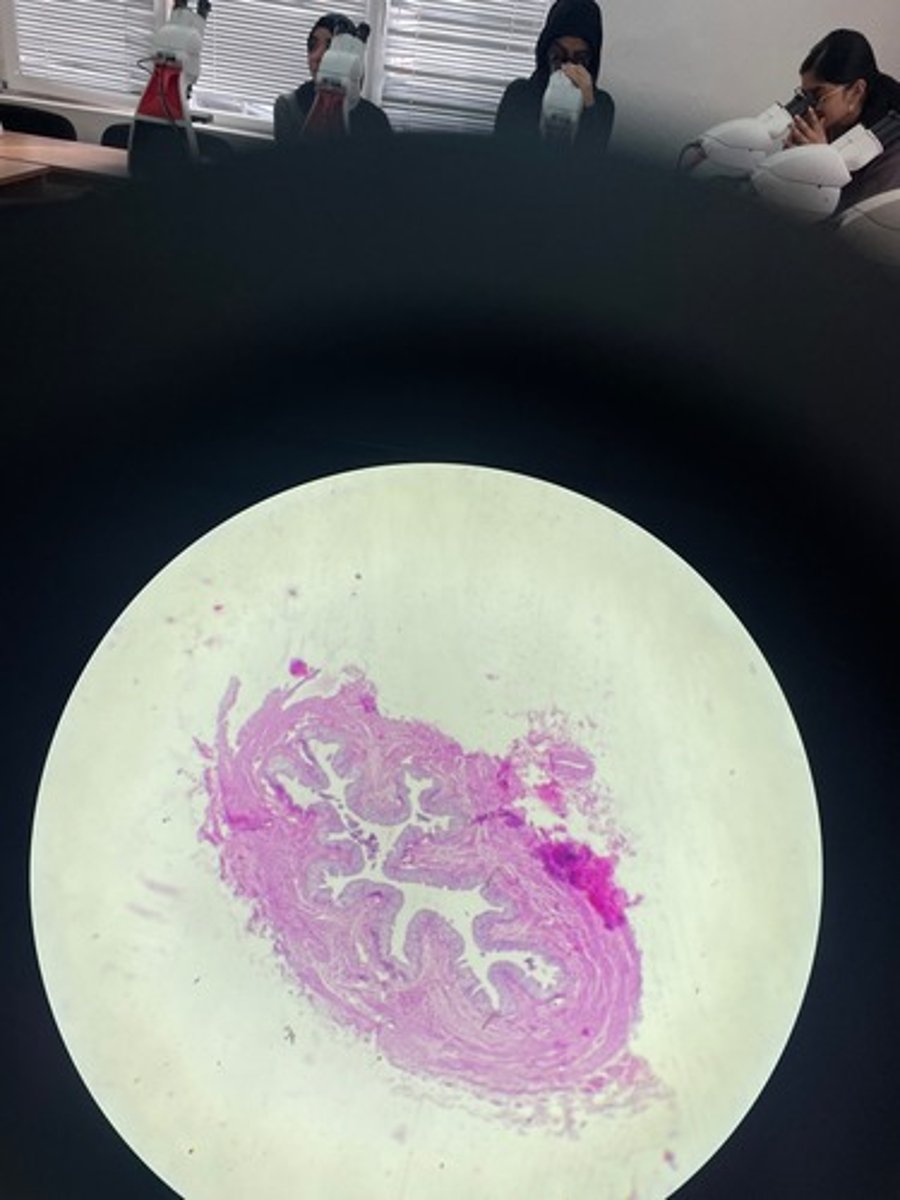

Ureter HE

Ureter HE

Ureter HE

Ureter HE

Ureter HE